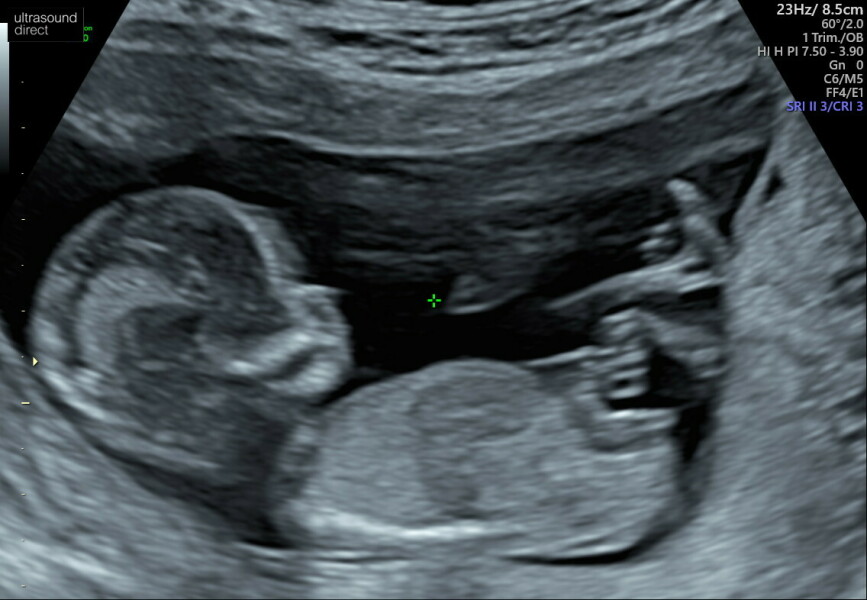

@BB2818 all good over here! 26+2 and getting excited now to be honest. All seems well so far, got a private 4d scan on the 13th to take my son to 😊.